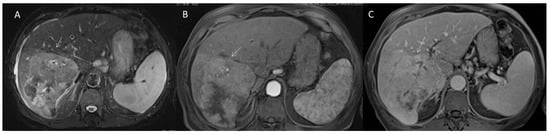

2.2.5. LR-M Category

2.3. CEUS-LI-RADS